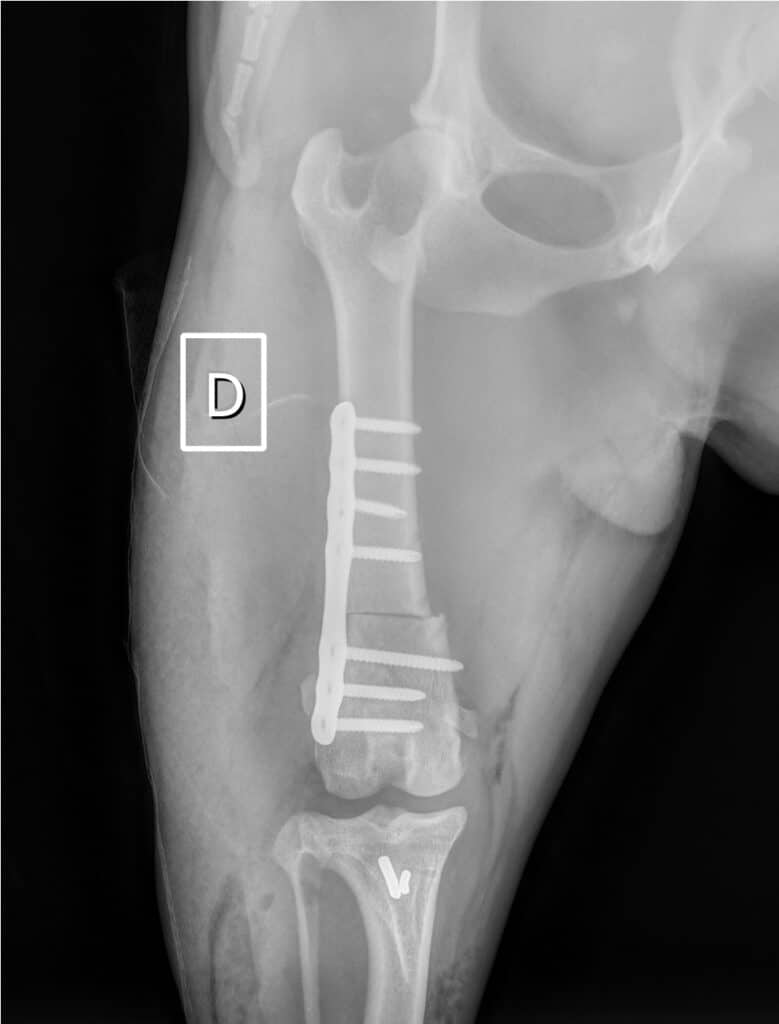

Dans le cas de notre bouledogue qui présentait des déformations osseuses marquées, une ostectomie fémorale latérale dite en « closing wedge » est réalisée en plus des techniques « classiques » présentées ci-dessus. Elle permet de corriger le varus et la torsion, en fixant avec une plaque le fémur proximal et distal, réalignés pour obtenir un angle d’antéversion dans les normes (18°). Les ostéotomies fémorales et tibiales permettent un résultat optimal lorsqu’elles sont indiquées et permettent d’obtenir un très faible taux de récidive de luxation.

Dans le cas de notre bouledogue qui présentait des déformations osseuses marquées, une ostectomie fémorale latérale dite en « closing wedge » est réalisée en plus des techniques « classiques » présentées ci-dessus. Elle permet de corriger le varus et la torsion, en fixant avec une plaque le fémur proximal et distal, réalignés pour permettre un angle d’antéversion dans les normes (18°). Les ostéotomies fémorales et tibiales permettent un résultat optimal lorsqu’elles sont indiquées et permettent d’obtenir un très faible taux de récidive de luxation.

Au contrôle à deux mois et demi, le chien ne présente plus de boiterie, une rotule stable et en place et la guérison osseuse est complète sur les radiographies. Un retour à l’activité sur 4 semaines est alors préconisé.